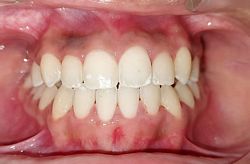

Intra-oral : Pre-treatment : Frontal View

Intra-oral : Post-treatment : Frontal View

Intra-oral : Pre & Post treatment : Frontal View : 10 mm Overjet Reduced